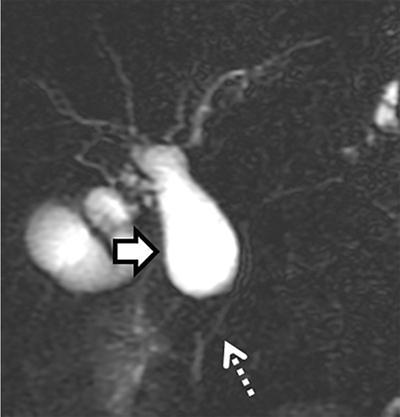

Observations: MRCP image showing the dominant dorsal duct of Santorini (arrows) draining separately into the minor papilla. The common bile duct (CBD) is joining the smaller ventral pancreatic duct through the major papilla.

MRCP image of ansa pancreatica in a 43-year-old male. The proximal dorsal duct connects with an inferior branch of the ventral duct (dashed arrow) through S-shaped collateral. (arrowhead)

2D MRCP image showing the pancreas is being drained by the dominant dorsal duct, which is crossing the CBD and draining at the minor duodenal papilla. In addition, there is focal dilatation (arrow) of the dorsal duct near the papilla consistent with Santorinicele.

2D MRCP image showing congenital choledochal cyst (arrow) with a long common channel (dashed arrow) joining the CBD.